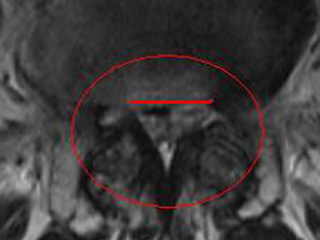

Der chirurgische Eingriff wird mit einem Zugang von Rücken aus durchgeführt und es werden alle Strukturen (Knochen, gelbe Band (Ligamentum flavum), Bandscheiben etc.) entfernt, die auf das Rückenmark, Nervenwurzeln und -bahnen drücken.

- Dekompression des Spinalkanals: Entfernung der Kompression der Nervenwurzel durch Vergrößerung der Nervenwurzelaustrittsöffnungen.

- Laminektomie: Entfernung des hinteren Anteils der Wirbelsäule und damit Vergrößerung des verfügbaren Platz für das Rückenmark. Dieses Verfahren wird bei schweren Stenosen angewendet.